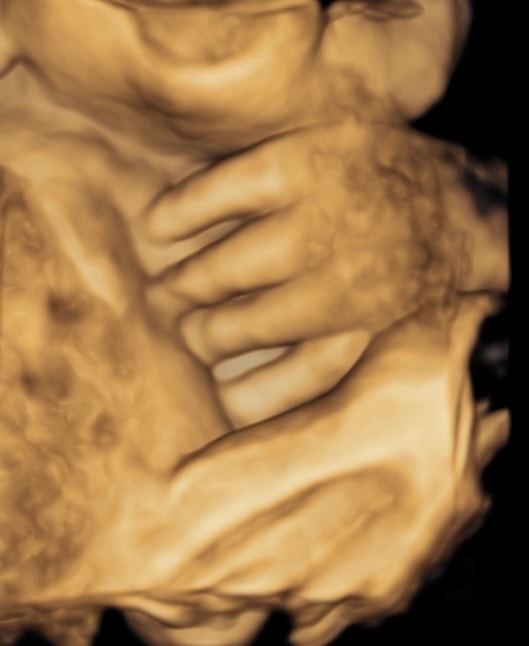

Tatiana, а зачем тогда пишут патологию, если могут написать, что не визуализируется? На хорошем оборудовании все очень четко видно, мне и стопы с пальчиками показали, и ладошки, и кулачки - можно сосчитать пальчики. Вот фотки 3д (делали просто для меня). Даже когда бесплатно делала, врач просила пойти погулять, поесть, чтоб малыш перевернулся, если не смогла что-то рассмотреть. В общем, странная история, слава богу все хорошо Изображение Изображение

Tatiana, вот где пальцы одной длины, это в Ставрополе делали на экспертнике, остальное Ростов, вот такие диагнозы мне ставили фото где все слиплось это в ПЦ смотрели, когда синдактилию поставили Последнее фото, узи за очень дорого в Ростове Я думаю, что давать оценку как видит врач не стоит, но в данном случае, я очень рада, что супер модный эксперт и спец в своем деле ошибся Изображение Изображение Изображение